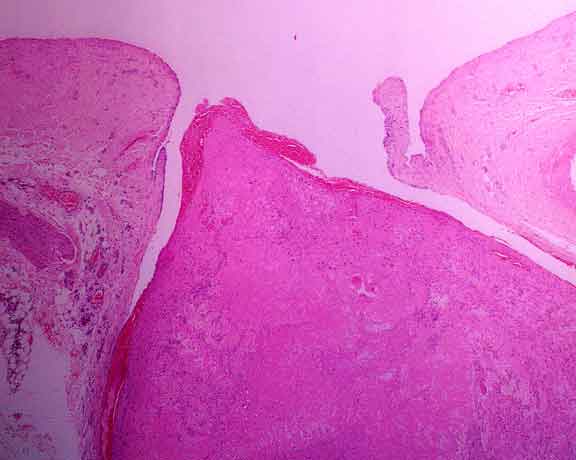

LOW POWER

An almost completely occlusive thrombus is present in a branch of the external jugular vein. Note the valves at the point where the vein branches.